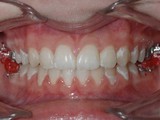

Zkřížený skus, předkus, nedostatek místa pro špičák. Léčba pomocí aparátu Hyrax a dále fixními aparáty v obou čelistech s jumping aparátem. V ústech přítomné MARA-stopy na dočasnou stabilizaci výsledku.

Před léčbou        Po léčbě

přední pac2        přední pac2